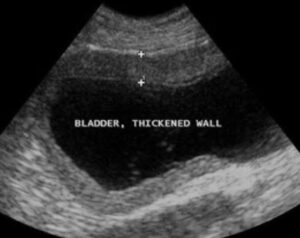

↑ 上の写真は、猫ちゃんの腸間膜リンパ節(LN)です。・■ 黒色の楕円形部分は、腸間膜リンパ節が腫脹しています。・■ ここは、FIPを除外するための細胞診検査のサンプリングの推奨部位です。 参照サ…